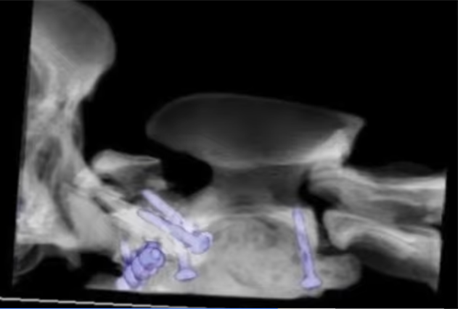

A combination of SOP plate, screws and bone cement were carefully used - with great precision - to realign and stabilise Poppy’s fracture. She was then hospitalised in high dependency unit for several days.

poppy surgical fix